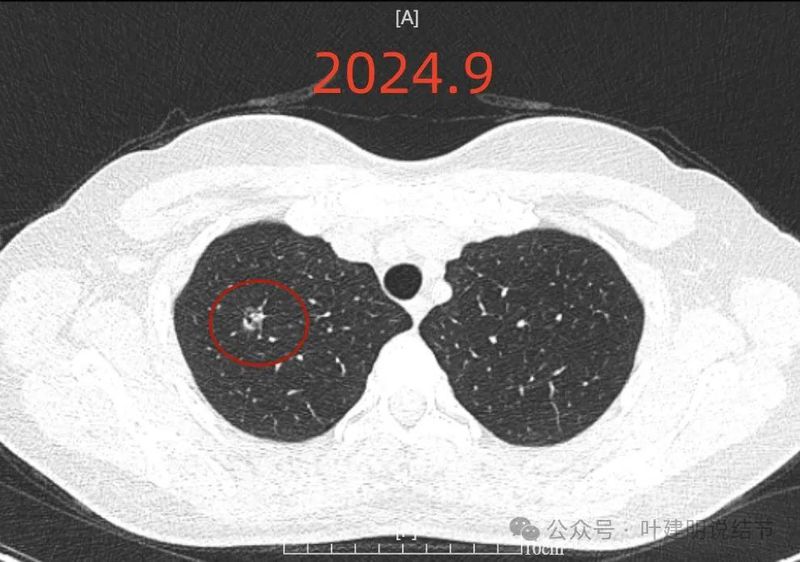

先看2024年11月份的影像:

右上叶磨玻璃结节,轮廓较清,密度较淡,有小血管进入。

表面不平,分叶明显,灶边有小空泡征,灶边另有多处血管贴边,也见血管分支进入。

病灶密度稍不均,分叶明显,中间有扩张的细支气管,血管有贴边。整体轮廓与瘤肺边界清。

有实性成分出现。

混合密度,月牙铲征,轮廓清,血管多支进入,灶内实性成分明显,表面不平分叶,灶内细支气管扩张。

分叶状明显,支气管扩张明显,血管弯征可见,整体轮廓清。

灶内支气管扩张,附近血管有异常增粗,表面不平。

形态不规则、轮廓与边界清、多支血管进入穿行、支气管扩张,表面不平。

磨玻璃密度伴灶内支气管扩张。

支气管扩张,病灶磨玻璃密度,有血管进入穿行。

边缘处密度较淡。

2024年7月时此灶已经在,而且密度不纯,整体轮廓与边界清。当时就是典型恶性的影像表现。

2024年9月病灶仍在,实性成分较前略显明显,矢状位清楚显示穿行血管壁毛糙。冠状位显示分叶以及病灶与血管间没有间隙。